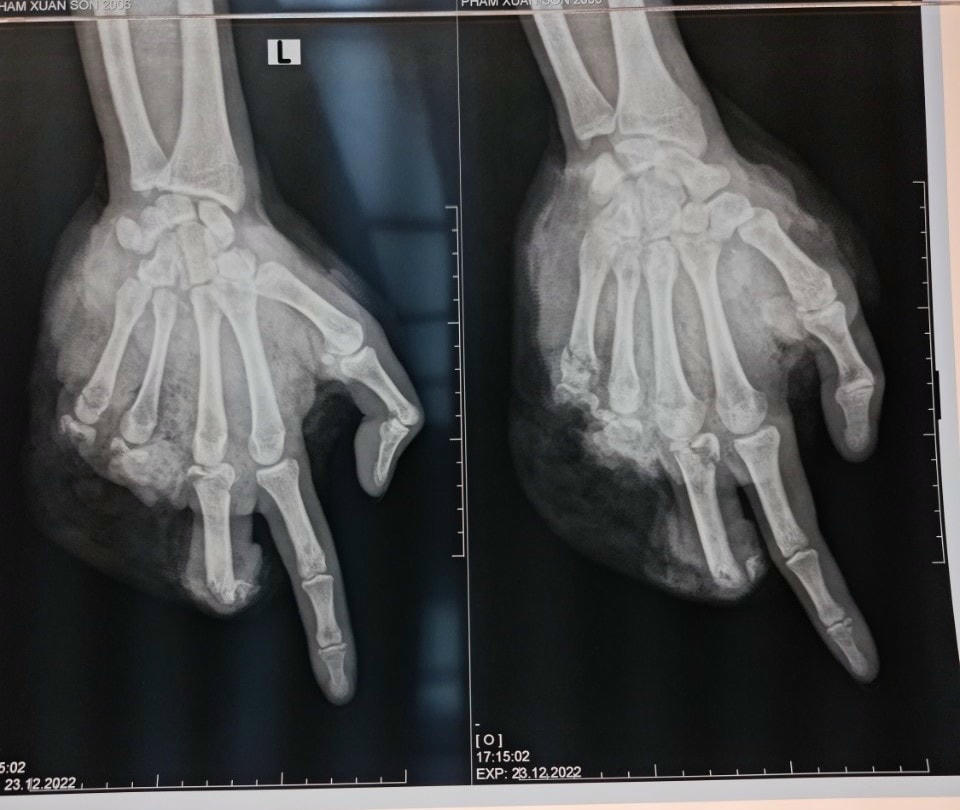

Một trường hợp điển hình được các bác sĩ thông tin, bệnh nhân nam (16 tuổi, ở Bắc Giang) vào viện trong tình trạng vết thương bàn tay trái phức tạp. Theo lời kể của gia đình, bệnh nhân chơi pháo tự chế, khi đang cầm pháo trên tay thì pháo nổ gây nát bàn tay trái và chân phải.

1 trường hợp khác cũng tại cơ sở y tế này, bệnh nhân nam (15 tuổi, ở Nam Định), bệnh nhân bị nát bàn tay phải, gãy đốt 1 ngón tay phải, vết thương chảy máu phức tạp. Tại Bệnh viện 108, bệnh nhân được các bác sĩ kịp thời phẫu thuật cấp cứu, xử lý vết thương. Các bác sĩ tiến hành phẫu thuật cắt lọc vết thương, chỉnh trục các ngón, găm đinh cố định, khâu định hướng vết thương, hiện tại bệnh nhân tỉnh táo,….